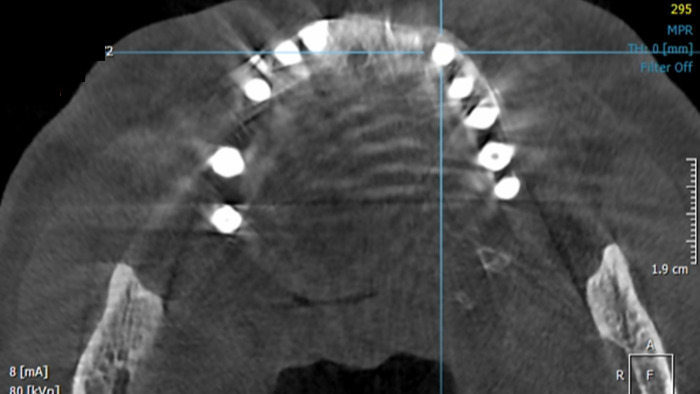

Clinical case: Peri-implantitis treatment case using titanium or NiTi brush

- Courtesy of Dr. Dae-Hee Lee, South Korea -

Dr. Dae-Hee Lee,Maxillary Anterior,Peri-implantitis,Bone regeneration,Aesthetic zone,#21,#22,GBR,Titanium Brush Set